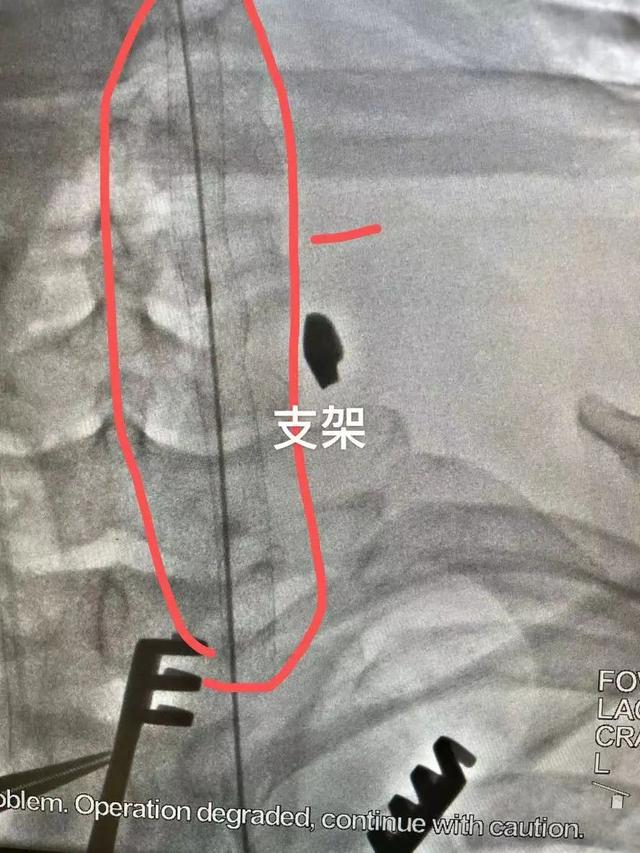

根据陈先生的病史和术前CT影像,赵文军手术团队迅速制定好了手术方案。“分两步走,先用支架从里面堵住血管破损处,再从颈部开刀进去修补血管。”

使用的支架,全称是人工血管覆膜支架,从大腿根部处通过穿刺血管置入,送到颈动脉破损处。这是介入手术范畴,需要医学影像引导,杂交手术室为患者节约救命时间的优势这时就显现出来了。

当支架在陈先生颈部顺利打开,相当于给颈动脉穿了一件“内甲”,完美堵住了出血口。

“外围血肿清除后,能看到长约1厘米的颈动脉破口,还能看到里面的人工血管覆膜支架。”赵文军说,手术视野清晰,能让外科医生更快速地完成缝合。